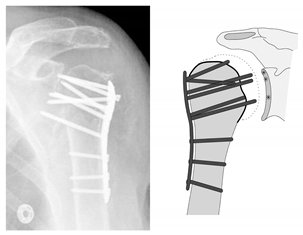

| Complication Type | Exemplary Images by X-rays or Pattern Images | Definition |

|---|---|---|

| 3 | ![]() | Type 3 describes a displacement of the angular stable plate osteosynthesis with screw cutout/fracture avulsion in the humeral shaft region, while the humeral head position remains intact. |

| 4 | ![]() | Complication Type 4a is based on the presence of AVN of the humeral head without concomitant destruction of the glenoid articular surface due to an associated screw cutout through the humeral head cortex. |

| 4b | ![]() | Complication Type 4b is also based on the presence of an AVN of the humeral head combined with a destruction of the glenoid articular surface due to the associated screw cutout through the humeral head cortex. |